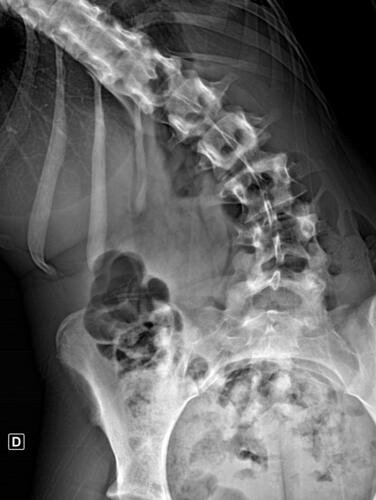

A Vá tem 13 anos e precisa urgentemente realizar uma cirurgia na coluna.Valentina foi surpreendida com o diagnóstico de escoliose hepática grave com 67 graus de desvio (desvio longitudinal da coluna), e precisa realizar com urgência a cirurgia corretiva, os exames foram realizados em Porto Alegre, mas a cirurgia está marcada para dia 13/07 em São Paulo devido a gravidade do caso, para isso a família terá que ficar residindo próximo ao hospital em São Paulo por no mínimo 30 dias para uma plena recuperação. Sabemos bem que qualquer procedimento cirúrgico é delicado, na coluna então nem se fala.Após o diagnóstico e o prognostico dessa doença a família se desfez de alguns bens (carro e moto) para cumprir os prazos dos exames e consultas, necessitando agora arrecadar o valor para a estadia da pequena Valentina e seu pós operatório (medicação, consultas e fisioterapia).

Em anexo os exames (laudo e imagens) para expressas a gravidade do caso.